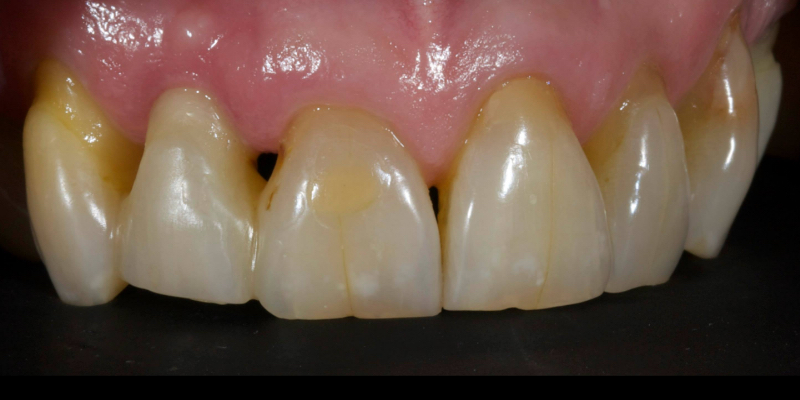

Take Arthur, a 76-year-old man who presented with a vertical root fracture of his upper left central incisor. His medical conditions precluded his request for an implant, so he agreed to the proposal for an adhesive bridge instead.

The tooth was extracted and for four months the pontic site was conditioned with a removable Essix-type of denture (Fig. 1).

An e.max (lithium disilicate), one-wing (adjacent central being the retainer) bridge was placed, which resulted in an acceptable outcome (Figs. 2-4) that was more timely and at a lower financial and biological cost to the patient than the implant Arthur initially thought he wanted.